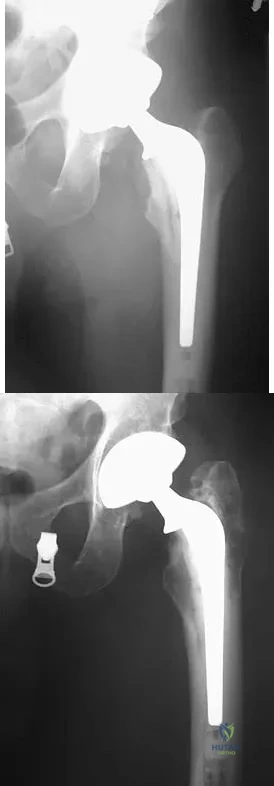

A 51-year-old male truck driver has had progressive left hip pain for more than 2 years, and he reports that the pain has become severe in the past 9 months. He is now unable to work because of the pain. Examination reveals that range of motion of the hip is limited to 95 degrees of flexion, 0 degrees of internal rotation, and 20 degrees of external rotation. The plain radiograph, MRI scan, and intraoperative gross photographs are shown in Figures 9a through 9d. Management should consist of

Explanation

Figure 17 shows the radiograph of an 80-year-old woman who has left groin pain. She underwent a total hip arthroplasty 15 years ago and has no history of hip dislocation; however, she now reports that the pain results in functional impairment. Preoperative findings reveal that the component used has been discontinued, the locking mechanism is poor, and there is no replacement polyethylene available from the company. During surgery, the acetabular component is found to be well fixed, it is in satisfactory position, and adequate access can be obtained through the screw holes in the component to debride the osteolytic cavities. What is the best course of action for revision?

Explanation